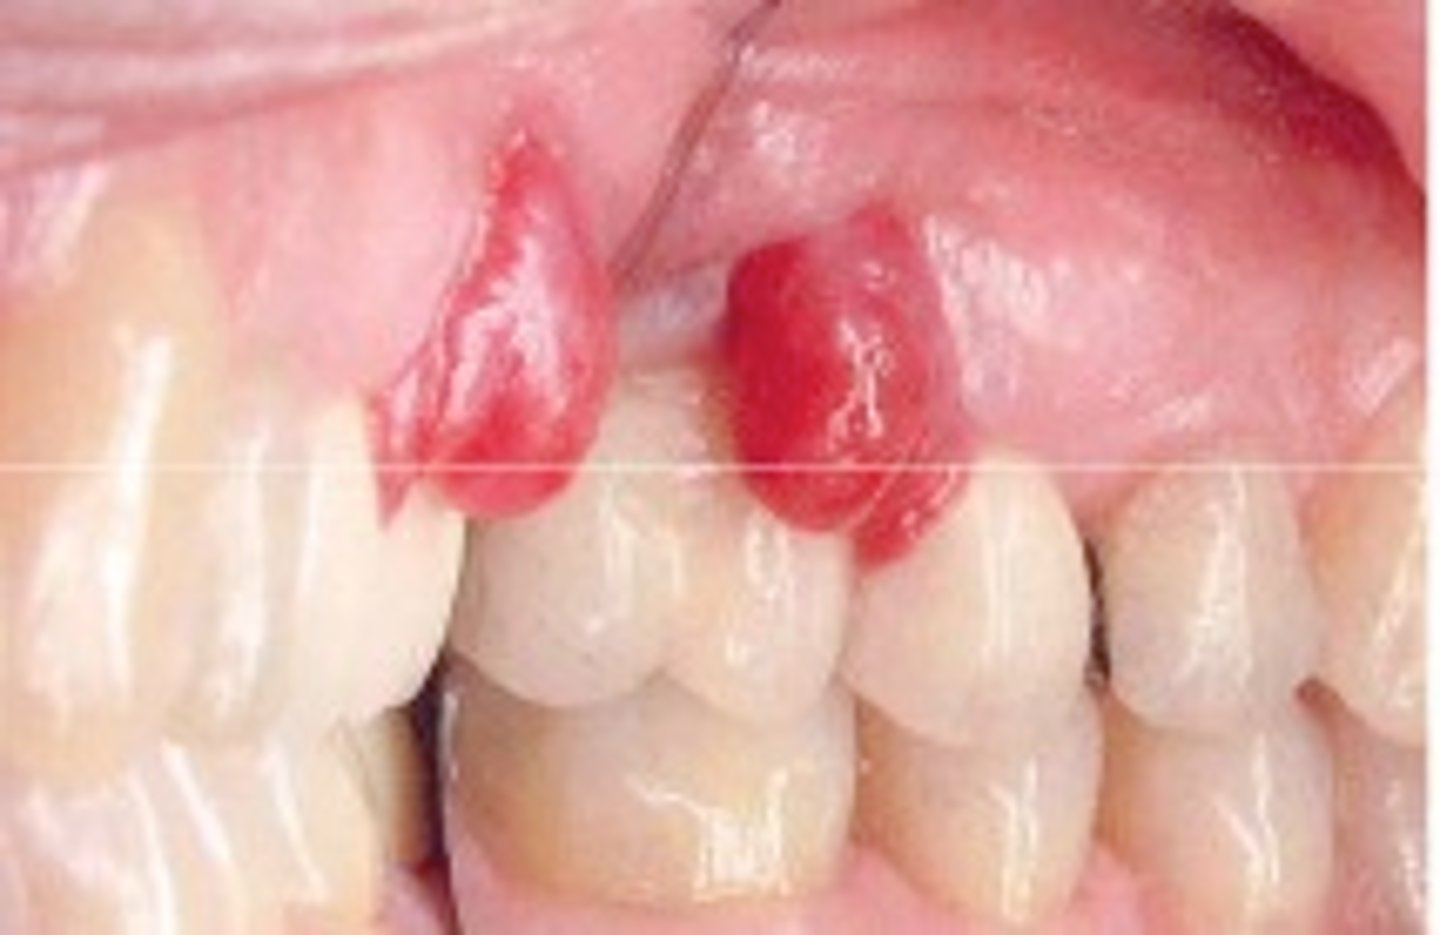

How do you determine is it Pyogenic granuloma or a Peripheral giant cell granuloma?

This can be hard to distinguish. The appearance of peripheral giant cell granuloma is similar to pyogenic granuloma. Peripheral giant cell granulomas color ranges from red to bluish -purple, but is usually more blue in comparison to pyogenic granulomas. It can be sessile or pedunculated with the size usually being less than 2cm.

Pyogenic granuloma

Small, reddish bumps on the skin that bleed easily due to an abnormally high number of blood vessels. It is a primarily oral disease which appears as an overgrowth of tissue due to irritation, physical trauma or hormonal factors. It is not an infectious but a reactive lesion due to local irritating factors.

Peripheral giant-cell granuloma

An oral pathologic condition that appears in the mouth as an overgrowth of tissue due to irritation or trauma. It presents as a lobular, purplish-blue exophytic nodule exclusively on the gingiva, both edentulous and dentate, and usually anterior to the molars. It originates from the periodontal ligament or the periosteum. It occurs across a wide age range, commonly in children, young adults, and in females. It presents as sessile or pedunculated and smooth surfaced or lobular, and though usually painless it can occasionally be ulcerated, painful and accompanied by bleeding. Like pyogenic granuloma, it is usually present either on the buccal or lingual gingiva or between teeth, but it can occasionally surround the teeth and act aggressively by displacing teeth much like a sarcoma. It appears only on the gingiva or on an edentulous (without teeth) alveolar ridge. It is more often found in the mandible rather than the maxilla but can be found in either anterior or posterior areas. The underlying alveolar bone can be destroyed, leaving a unique appearance referred to as "cupping resorption" or "saucerization."

Peripheral giant-cell granuloma target population